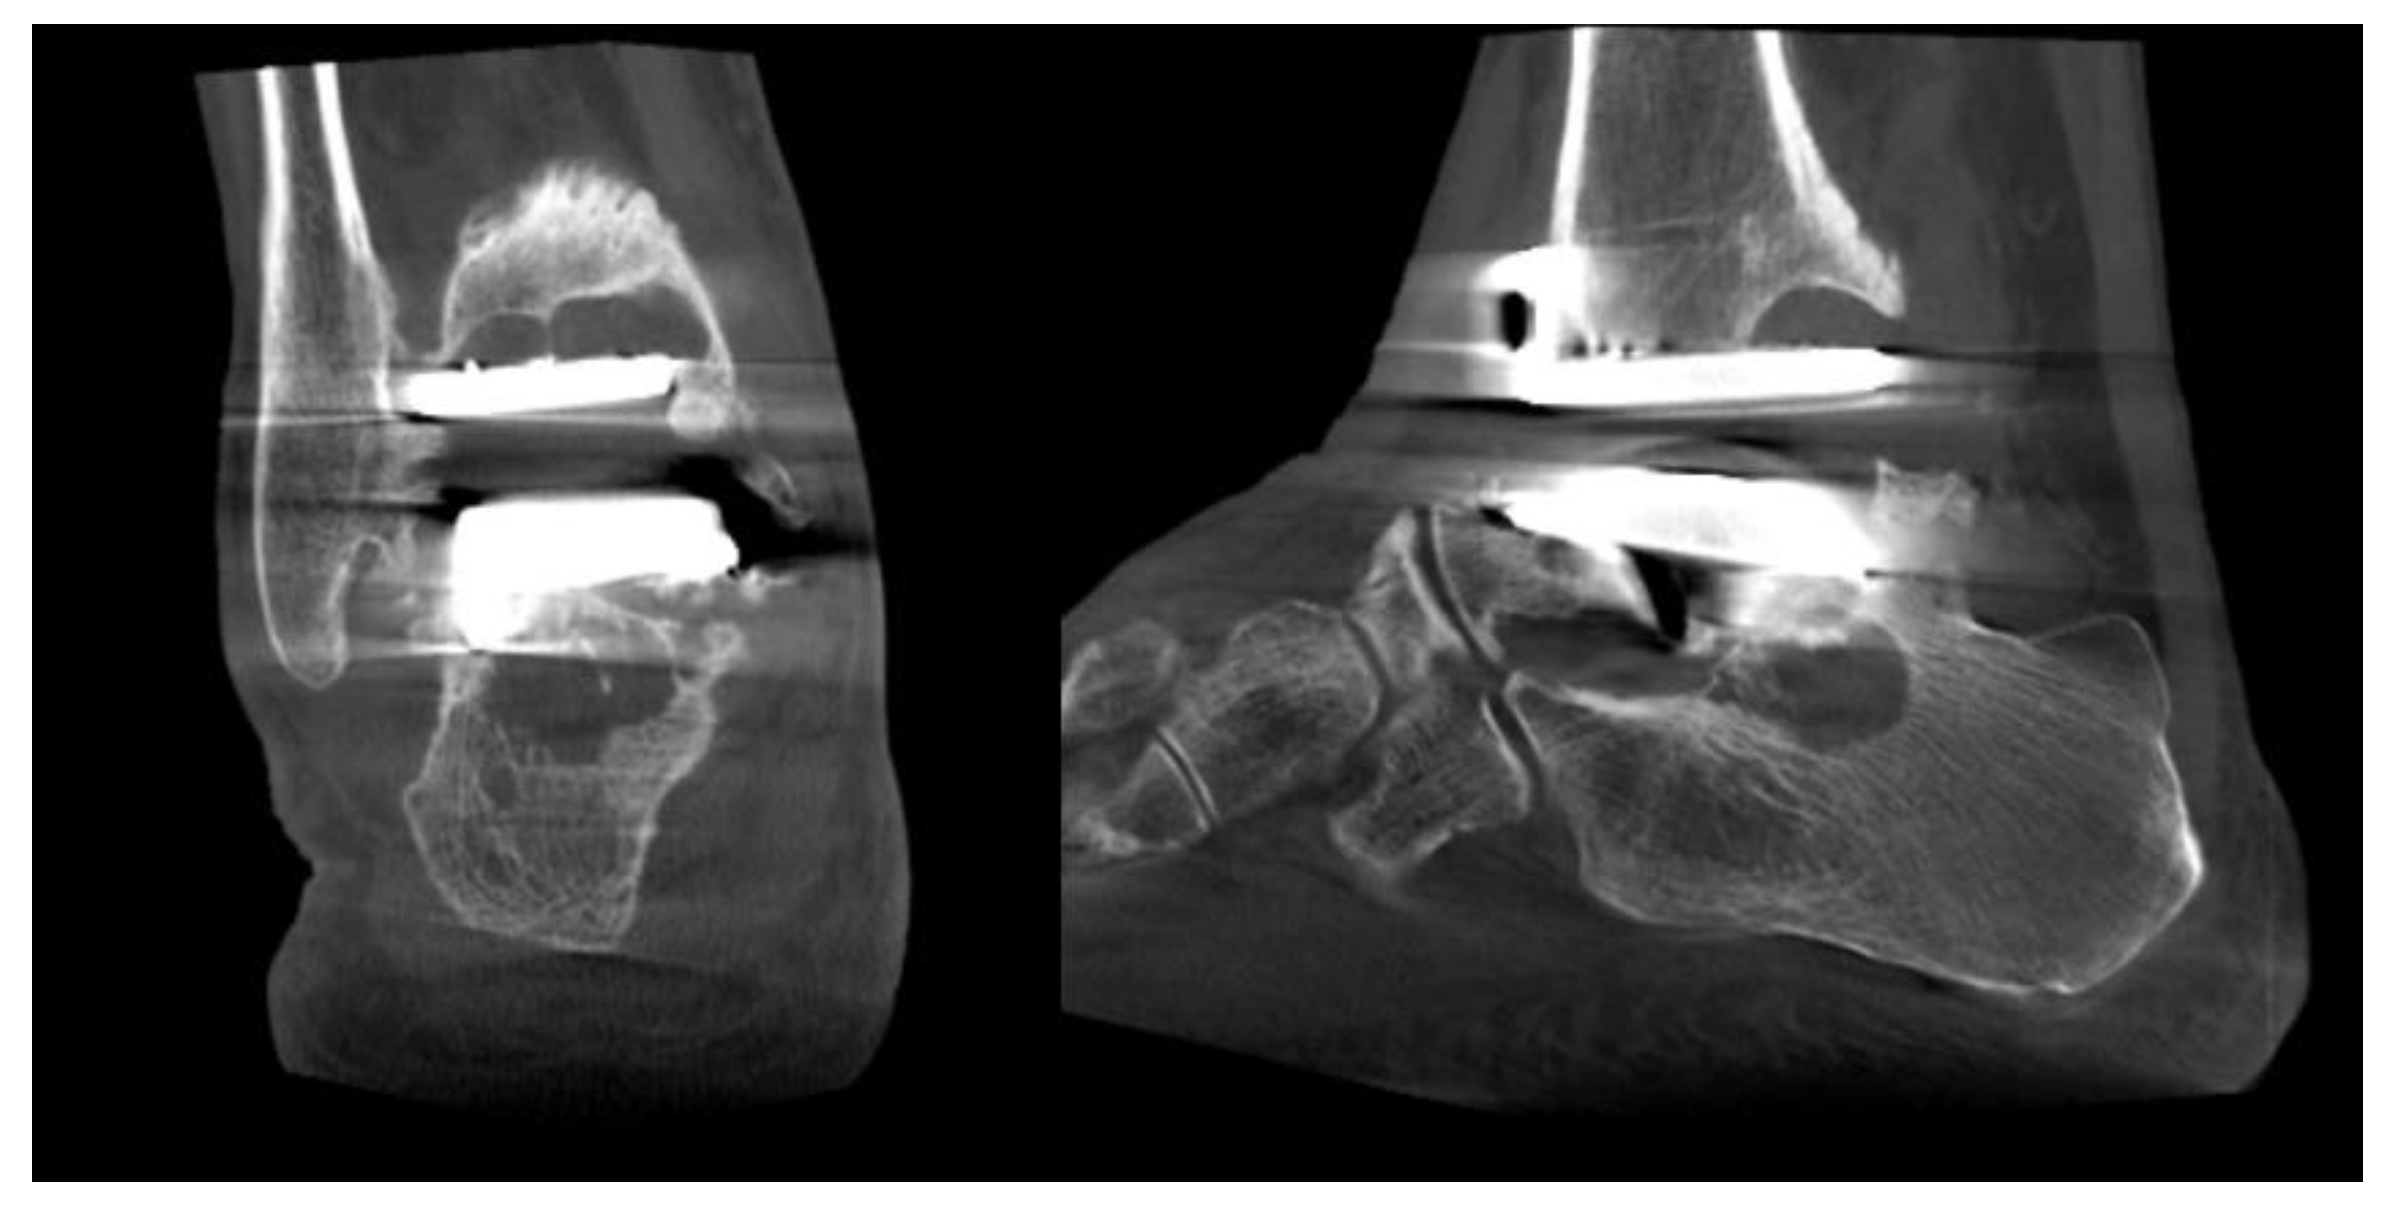

- Ankle replacement surgery